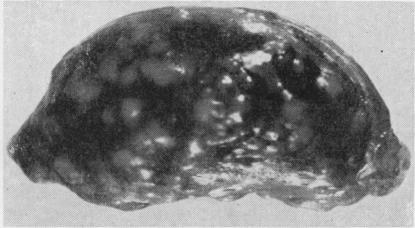

Myco. fortuitum was isolated from subcutaneous abscesses of two patients who had been inoculated with B.C.G. and one patient who had iron injections. The organisms were resistant to a wide range of anti-tuberculous drugs. They were highly virulent for mice in which they produced symptoms of spinning disease. It is thought that the infections originated from contamination of syringes or skin.

偶然分枝杆菌从两名接种过卡介苗的患者和一名接受过铁剂注射的患者的皮下脓肿中分离出来。这些菌株对多种抗结核药物耐药。它们对小鼠具有高度致病性,可使小鼠出现旋转病症状。据认为,感染源于注射器或皮肤的污染。